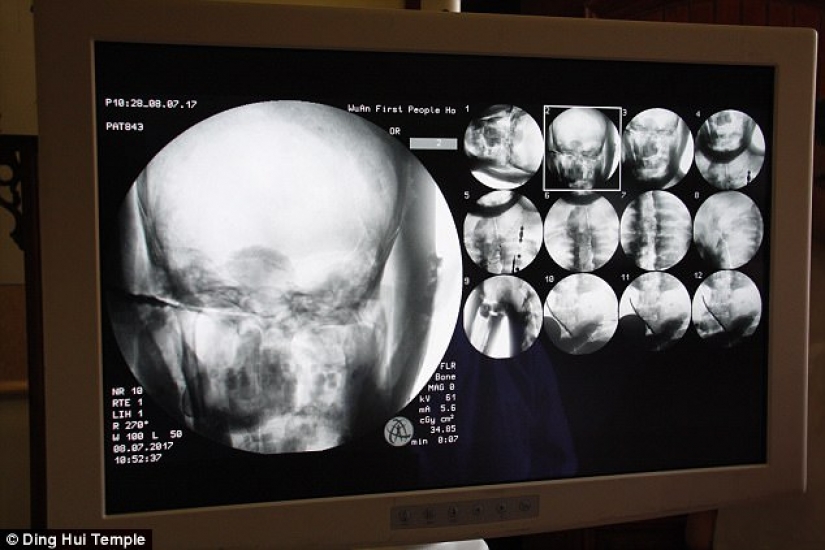

Por Pictolic https://mail.pictolic.com/es/article/una-momia-milenaria-de-un-monje-budista-tiene-un-cerebro-y-un-esqueleto-preservados-en-perfecto-estado.htmlEl cuerpo momificado de un monje budista de mil años todavía tiene los huesos y el cerebro intactos. Esto fue revelado por una tomografía computarizada.

El descubrimiento se realizó después de que los restos dorados del Maestro Ci Xian se sometieran a un examen médico en el Templo Dinghui en el norte de China.

La tomografía computarizada se realizó el 8 de julio. La gente se sorprendió cuando los médicos dijeron que el esqueleto y el cerebro de Ci Xian estaban en perfectas condiciones. "Podemos ver que sus huesos están tan sanos como los de una persona normal: la mandíbula superior, los dientes superiores, las costillas, la columna vertebral y todas las articulaciones están perfectamente conservadas. Esto es increíble", dijo el Dr. Wu Yongqing.